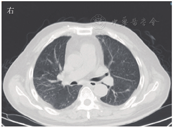

患者男,63岁,因"间断发热1年"于2020年6月29日入河南大学人民医院。患者1年前无明显诱因下出现发热,体温最高达38.0 ℃,伴有反应迟钝、吞咽困难、饮水呛咳、颈部硬肿,无咳嗽、咳痰,无胸闷、呼吸困难。患者于外院查血常规示感染相关指标高,CT检查示颅内感染可能(具体不详),予"美罗培南、万古霉素"抗感染治疗,体温可降至正常,但很快反复;后多次因"颅内感染"住院,予抗感染治疗,疗效差。4月余前因颅内高压、脑积水于外院行脑室-腹腔分流术。3月21日外院头颅MRI检查示左侧枕部颅板下积液、左侧颞枕顶叶明显水肿,增强后明显强化;颅脑术后改变。5月21日肺部CT检查示双肺多发结节影、条索影,考虑慢性炎症。为求进一步诊治来河南大学人民医院,门诊以"发热待查:颅内感染?脑室-腹腔分流术后"收入感染科。患者自发病来,神志欠清,精神差,食欲及睡眠可,二便正常,体质量较前无明显减轻。既往史:2003年因颈椎破坏行植骨术;2013年因"发热伴头痛"发现颅内病变,曾就诊于多家医院均未明确诊断,病情缓慢进展;2018年因"头痛加重"行颅内病变切除术,术后考虑感染性病变,间断抗感染治疗,病情仍无改善。体格检查:体温为36.8 ℃,脉搏为88次/min,呼吸为20次/min,血压为135/85 mmHg(1 mmHg=0.133 kPa)。神志欠清,反应迟钝,对答欠切题,计算力下降。双侧额纹变浅,闭目力差,双侧鼓腮力、咀嚼力差;伸舌困难,舌不能完全伸出;双侧瞳孔等大等圆,眼球活动度差,尤其上视、右视时明显,对光反射迟钝,视力下降;颈部红肿、僵硬,无压痛;双肺听诊呼吸音清,未闻及干、湿啰音;心前区无隆起,心界不大,律齐,各瓣膜听诊区未闻及心脏杂音及心包摩擦音;腹部平软,无压痛,肝脾肋下未及,移动性浊音阴性,肠鸣音正常;双下肢无水肿,肌力3级,腱反射(-),病理征(+)。考虑为免疫性疾病,予补液、营养支持等对症治疗。实验室检查:IgG为37 910 mg/L,抗髓过氧化物酶抗体为24.21 RU/mL,IgE为208.3 IU/mL,IgG4为10 400 mg/L;IL-6为115.88 ng/L;ESR为106 mm/1 h;CRP为146.36 mg/L;降钙素原为0.12 μg/L;血常规、尿常规、粪便常规、游离三碘甲腺原氨酸、游离甲状腺素、促甲状腺激素、T.SPOT.TB检测、β-D-葡聚糖试验、半乳甘露聚糖抗原试验、EB病毒DNA、CMV DNA、布鲁菌抗体、肿瘤标志物均阴性。6月30日胸部CT检查示双肺多发结节,见图1。7月2日头颅MRI平扫+增强检查示脑内多发异常信号影;后纵裂池处脑膜、小脑幕及左侧颞部硬脑膜增厚并明显强化;左侧枕叶局部脑穿通畸形形成,见图2。进一步行腰椎穿刺脑脊液检查示单核细胞计数为66×106/L,蛋白质为6.02 g/L,葡萄糖为2.02 mmol/L,氯化物为119.9 mmol/L。考虑为IgG4相关疾病(immunoglobulin-G4 related disease,IgG4-RD)。7月2日请病理科会诊外院术中脑组织病理切片,结果示(左枕)纤维组织增生伴玻璃样变性,局部胶原化,淋巴袖套结构可见,血管周围及硬化间质内见较多淋巴细胞及浆细胞浸润,浆细胞形态成熟,见图3;免疫组织化学染色示纤维及血管周边可见多量IgG4+浆细胞浸润,IgG4+浆细胞约为50~100个/高倍视野,见图4。根据患者检查结果和多科室专家会诊,诊断为IgG4-RD,累及中枢、肺部、皮肤、骨骼。由于患者病变侵犯脑干,有脑水肿、颅内压升高等表现,可能出现呼吸、心跳骤停等严重并发症,与患者家属沟通患者病情。7月10日开始予甲泼尼龙(500 mg,1次/d,静脉滴注)冲击联合丙种球蛋白(20 g,1次/d,静脉滴注)治疗。当天患者眼球转动基本正常,进食无呛咳,意识、反应和言语明显好转,颈部硬肿好转。予静脉滴注甲泼尼龙500 mg 3 d、240 mg 3 d、120 mg 3 d、80 mg 3 d、40 mg 3 d,以及静脉滴注丙种球蛋白20 g (1次/d) 5 d,患者症状明显改善,复查IgG、IgG4、ESR、CRP均较前下降。7月13日肺部CT检查示双肺结节明显缩小,见图5。7月19日头颅MRI检查示颅内局部脑水肿减轻,后纵裂池处脑膜、小脑幕及左侧颞部硬脑膜病变缩小,见图6。患者症状逐渐好转,7月24日患者及家属要求出院。出院后继续予甲泼尼龙治疗,后联合吗替麦考酚酯,患者一般情况稳定,定向力、记忆力、认知力正常,言语流利。